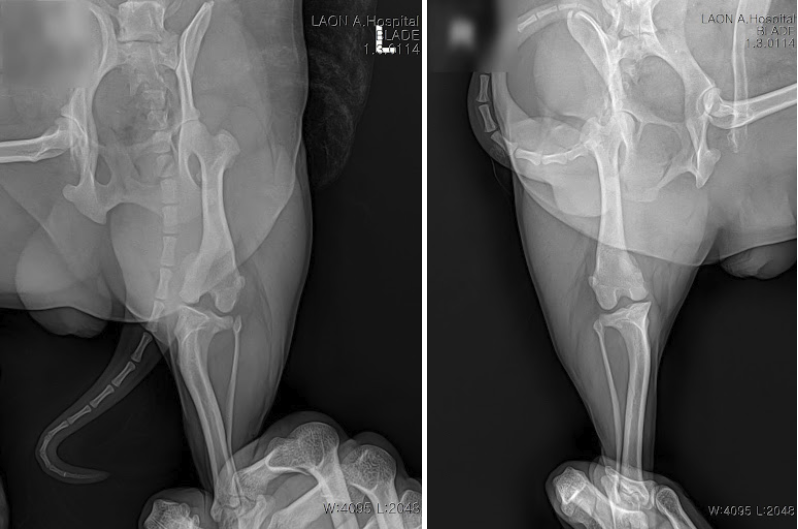

정확한 원인 파악을 위해 신체검사와 방사선 촬영을 진행했습니다.

수술 전 방사선 사진 / 출처: 라온동물메디컬센터

검사 결과, 양쪽 뒷다리 모두에서 슬개골 탈구가 확인되었고, 이미 관절염으로 인한 통증이 동반되고 있었습니다. 이 시기에는 무릎 관절에 만성 손상이 빠르게 진행될 수 있어, 수술적 교정이 필요한 상황이었습니다.